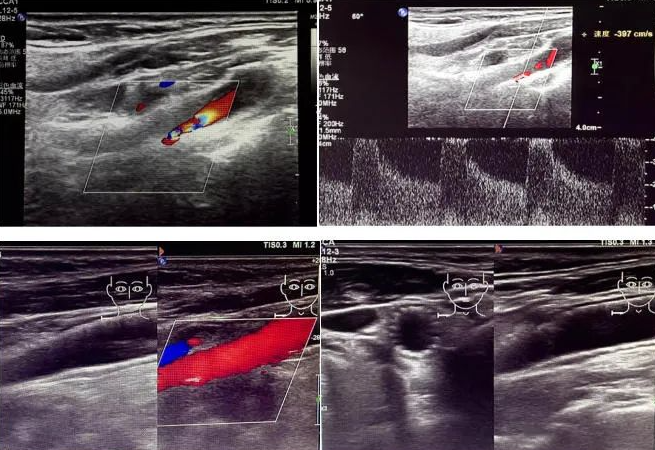

該患者因反復(fù)頭暈前來(lái)國(guó)文醫(yī)院就診。經(jīng)醫(yī)院超聲科運(yùn)用高端超聲設(shè)備進(jìn)行頸動(dòng)脈超聲檢查后發(fā)現(xiàn),其右側(cè)頸動(dòng)脈狹窄程度超過(guò) 90%。如此嚴(yán)重的狹窄狀況,猶如高速公路上的嚴(yán)重堵車,使得血液流通受阻,大大增加了腦梗死的風(fēng)險(xiǎn),時(shí)刻威脅著患者的生命安全。

頸動(dòng)脈超聲檢查作為一種無(wú)創(chuàng)、安全且準(zhǔn)確的篩查手段,在評(píng)估血管健康狀況方面發(fā)揮著重要作用。它能夠清晰地顯示血管的狹窄程度以及斑塊性質(zhì),為臨床診療提供可靠的依據(jù)。國(guó)文醫(yī)院超聲科配備的高端超聲設(shè)備,更為精準(zhǔn)診斷提供了有力支持。